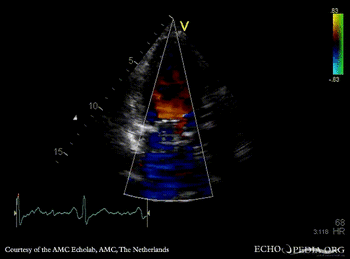

Mechanical mitral valve prosthesis

Courtesy of: AMC Echolab, AMC, The Netherlands

A3CH A3CH with Color Doppler